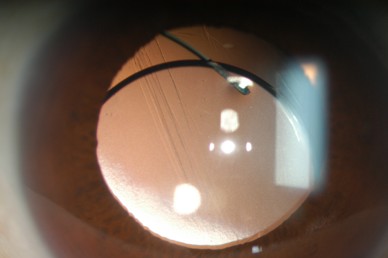

白内障手術によって固定された人工のレンズ(眼内レンズ)が本来の位置からずれてしまう状態のことです。

白内障手術後時間が経過すると、まれに(100人中1人程度)手術で固定した眼内レンズがずれたり外れたりすることがあります。周りの組織が加齢とともに弱くなることが原因です。その他に打撲などの外傷、強い近視、ぶどう膜炎などの炎症、網膜硝子体手術など他の手術の既往があるとレンズを支えている組織が弱くなることがあります。症状として、視力低下、二重に見えることや見え方が変わる(目の中でずれたレンズが動く)ことがあります。

ずれたレンズは自然に元の位置に戻ることはありません。眼内レンズを摘出して新しい眼内レンズを固定する手術が必要になります。この手術は通常の白内障手術よりやや難しく、時間がかかりますが、多くの場合手術後の経過は良好です。